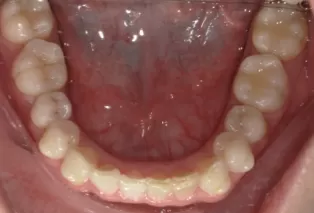

Intraoral photos